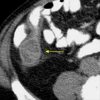

Mucocele ruột thừa

» Thông tin: Nam giới – 71 tuổi.

» Lâm sàng: Đau hố chậu phải mạn tính.